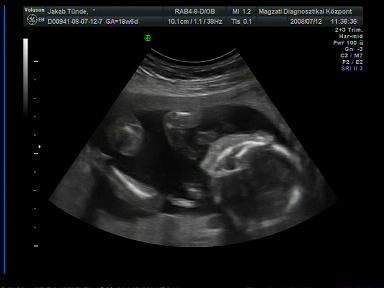

Jók a pocifotók!

Szeretnék segítséget kérni fizetős genetikai UH ügyben: ki hol járt és mennyire volt megelégedve a szolgáltatással? Ja, és a legfontosabb, hányadik hétig lehet menni ilyen genetikai UH-ra???

Ugyanis ma voltam a kórházban UH-n és kb. 3 perc alatt lerendeztek. A doki közlékeny volt, de nagyon rohamtempóban történt minden. Szóval hogy megnyugodjak teljesen, szeretnék elmenni egy alaposabb vizsgálatra is. A nemének beazonosításában is nagyon készséges volt doki bácsi, de Pötty szégyenlős volt (lehet, ez már utal valamire

) és jól összezárta a lábait. Amúgy az ő vizsgálatuk szerint minden ok. És medence végű, ami nem tudom, hogy jót jelent-e, mindenesetre a doki ezzel magyarázta, hogy nem tud sokat mocorogni, mert nincs túl sok helye ott.